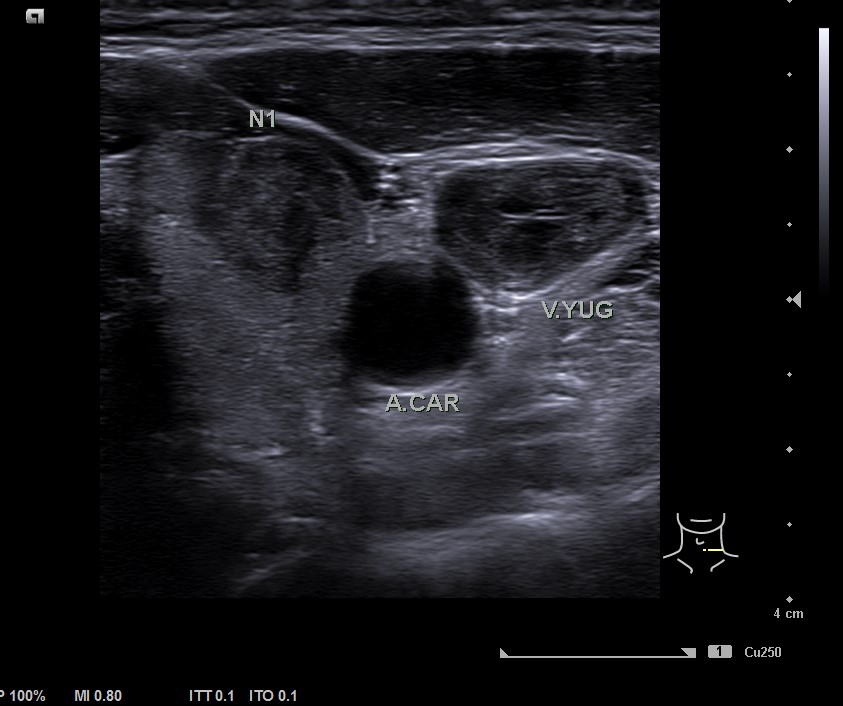

En la ecografía tiroidea se observa en LTI nódulo de 10 mm de bordes mal definidos, lobulado, mayormente sólido, más alto que ancho, isoecogénico, halo periférico hipoecoico, vascularización difusa, que sugiere TIRADS 5. Ausencia de flujo en Vena yugular interna izquierda, ensanchada, que sugiere trombosis yugular aguda o subaguda y junto a ella, posible conglomerado adenopático.